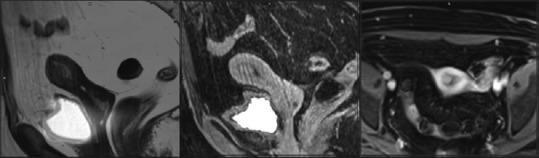

Paraneoplastic syndromes are a rare heterogeneous group of disorders that are indicators of the underlying occult malignancy. Subacute cerebellar ataxia in a patient with a known cancer is often due to metastatic invasion or other complications of the cancer, such as infection, coagulopathy, metabolic and nutritional deficits, or side effects of treatment. When tumor- and treatment-related causes have been excluded, the patient is considered to suffer from paraneoplastic cerebellar degeneration (PCD). We report a case of PCD that presented before any evidence of tumor, but early diagnostic workup and clinical vigilance helped us to find the underlying high-grade ovarian adenocarcinoma which was surgically removed later.

副肿瘤综合征是一组罕见的异质性疾病,是潜在隐匿性恶性肿瘤的指标。已知患有癌症的患者出现亚急性小脑共济失调,通常是由于癌症的转移侵袭或其他并发症,如感染、凝血病、代谢和营养缺乏或治疗副作用。当排除肿瘤和治疗相关原因后,该患者被认为患有副肿瘤性小脑变性(PCD)。我们报告一例PCD病例,该病例在出现任何肿瘤证据之前就已出现,但早期诊断检查和临床警惕性帮助我们发现了潜在的高级别卵巢腺癌,该腺癌后来通过手术切除。